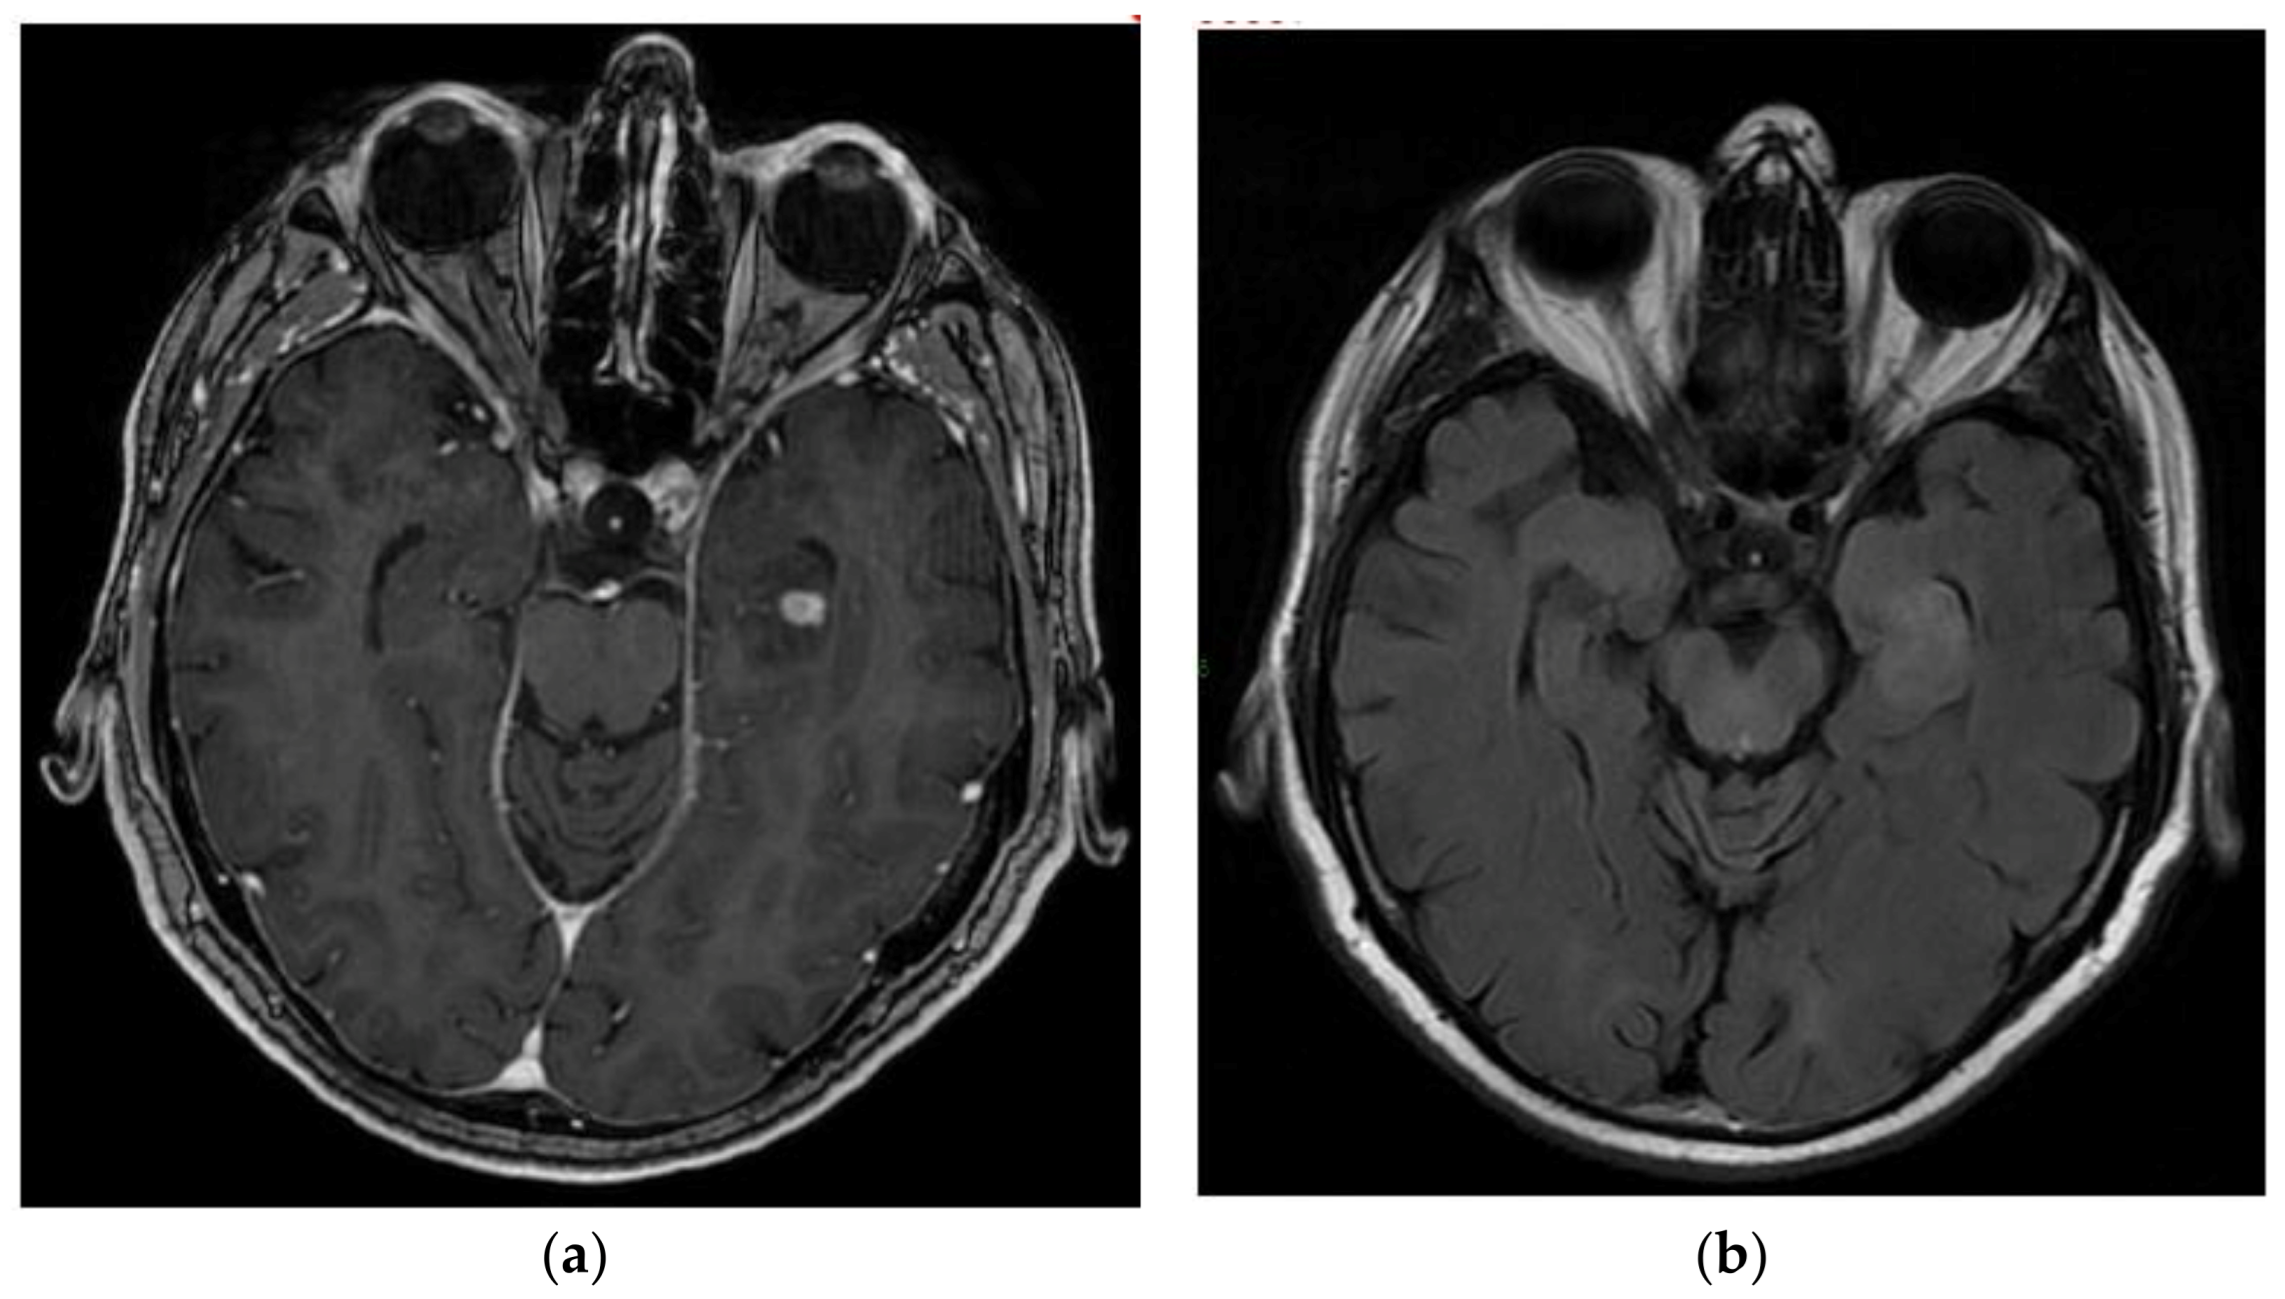

3.4. Cerebellar Liponeurocytoma

- Gembruch, O.; Junker, A.; Mönninghoff, C.; Ahmadipour, Y.; Oppong, M.D.; Sure, U.; El Hindy, N.; Lemonas, E. Liponeurocytoma: Systematic Review of a Rare Entity. World Neurosurg. 2018, 120, 214–233. [Google Scholar] [CrossRef]

- Kakkar, A.; Sable, M.; Suri, V.; Sarkar, C.; Garg, A.; Satyarthee, G.D.; Sharma, M.C. Cerebellar Liponeurocytoma, an Unusual Tumor of the Central Nervous System—Ultrastructural Examination. Ultrastruct. Pathol. 2015, 39, 419–423. [Google Scholar] [CrossRef]

- Xu, L.; Du, J.; Wang, J.; Fang, J.; Liu, Z.; He, Y.; Li, G. The clinicopathological features of liponeurocytoma. Brain Tumor Pathol. 2017, 34, 28–35. [Google Scholar] [CrossRef] [PubMed]